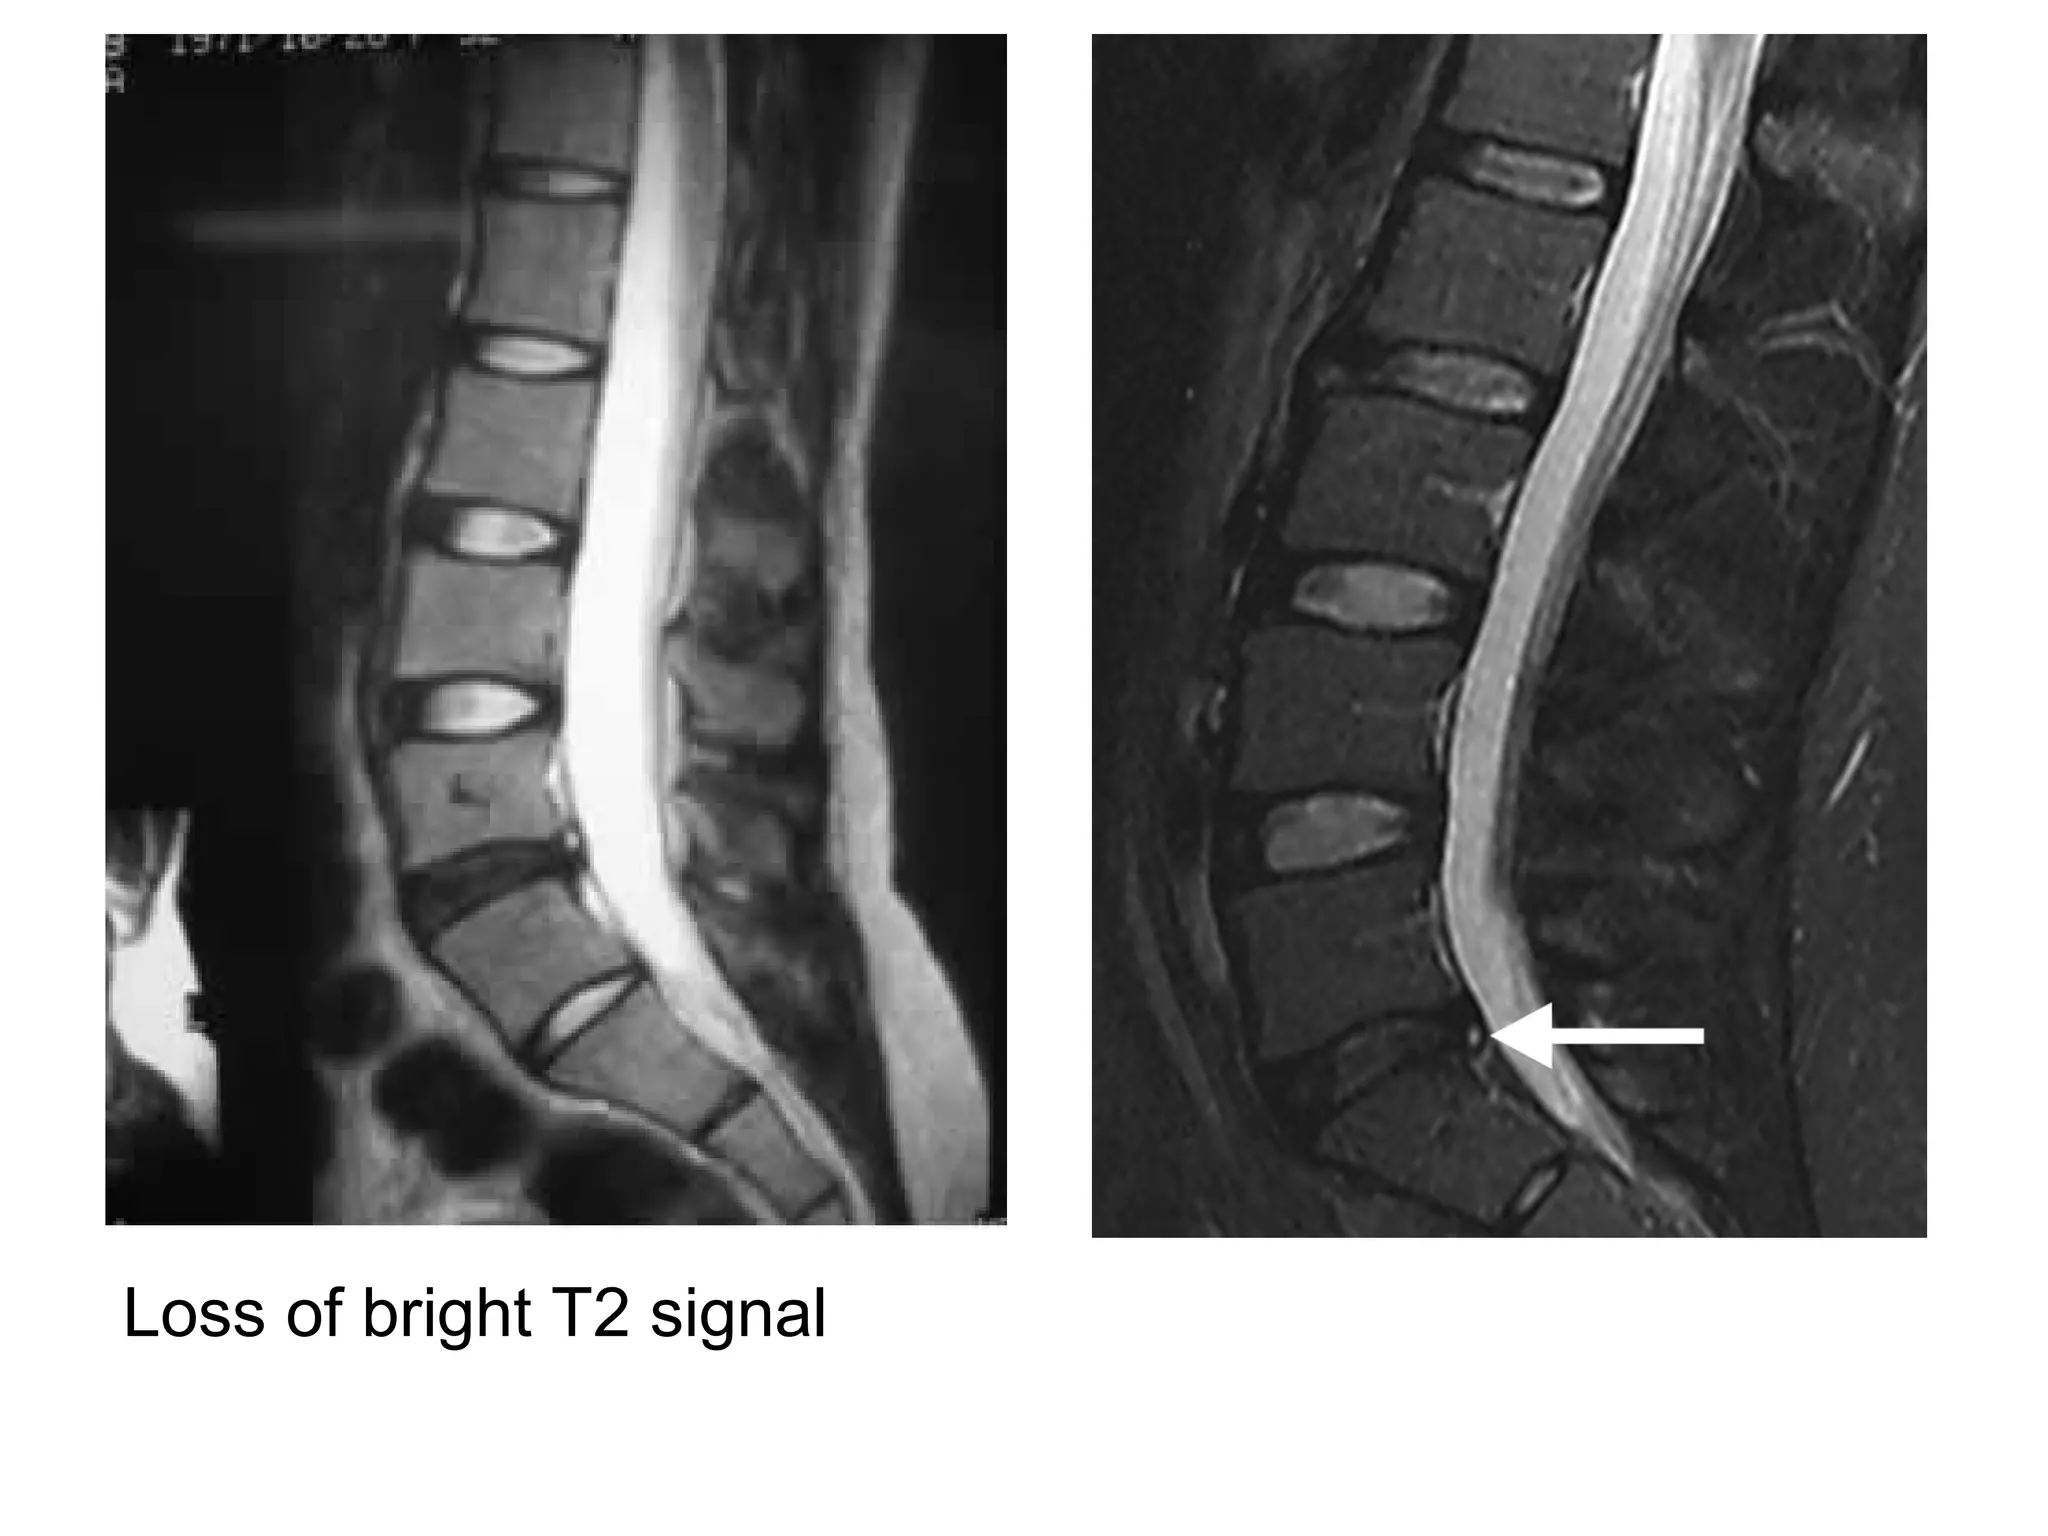

2-MRI :

-Disk signal abnormalities (loss of T2 bright signal)

indicate degeneration

Loss of bright T2 signal